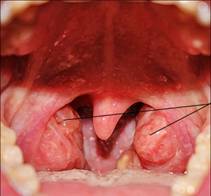

2. Ротовая полость: (слайд № 2)

- язык

- зубы

- твердое небо

- мягкое небо

- миндалины

Исходя из вышесказанного давайте определим, какие функции выполняет ротовая полость. (Обучающиеся дают ответы, учитель обобщает и делает вывод)

Миндалины находятся в складках мягкого неба и образуют лимфоидное глоточное кольцо, которое служит защитным барьером на пути инфекции. Установлено, что в них вырабатываются защитные вещества, которые воздействуют на проникших в организм микробов, разрушая их.

Все сказанное относится лишь к здоровым небным миндалинам. Если же в них развивается хроническое воспаление (тонзиллит), то защитные функции резко снижаются. Мало того, сами небные миндалины становятся очагом инфекции и могут провоцировать заболевания других органов и систем. В первую очередь сердца, суставов, почек, печени, и отягощать течение многих хронических заболеваний. Кроме того, такие миндалины становятся причиной аллергизации организма, тонзиллогенной интоксикации, для которой характерны бледность, вялость, быстрая утомляемость, снижение аппетита, субфебрильная температура.